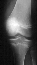

- XRAYS: Type III Meyer's / McKeever tibial spine fracture

CLASSIFICATION:

- Meyer's and McKeever have described three main types of intercondylar

fractures in children based on the amount of displacement and the fracture

pattern seen on the initial radiographs. Type I is nondisplaced and does

not interfere with knee extension. The type II fracture has a posterior

hinge with the anterior portion being elevated. In this type, knee extension

is generally limited, and there is a possibility that the anterior horn

of the meniscus is caught under the anterior fracture fragment. A type

III fracture is fully displaced, usually with the knee held in a mildly

flexed position.

RADIOGRAPHIC FINDINGS:

- Adequate AP and Lateral x-rays are essential to evaluate the degree

of displacement of the anterior tibial spine.

- Fracture is best seen on the lateral radiograph.